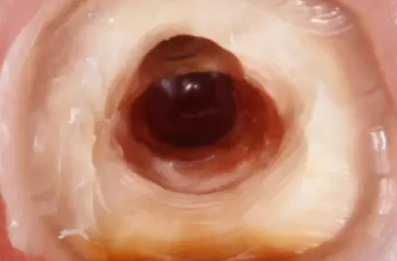

清理髓腔后,用中倍和高倍仔細(xì)查看穿孔的位置大小形狀和軟組織狀況。然后用小棉球?qū)⒏浇母芸诙氯。悦猱愇锏羧敫軆?nèi)。徹底清洗穿孔后,將調(diào)拌好的MTA材料充填到穿孔處,稍稍加壓,反復(fù)充填直到將穿孔填滿,使用小蒸餾水濕棉球整形,完成充填后,清理掉多余的材料,檢查外形。

然后用蒸餾水濕潤(rùn)的小棉球封入髓腔至少24小時(shí),待MTA完全硬固后完成根管治療。穿孔修補(bǔ)和根管充填完成后,要進(jìn)行嚴(yán)密地冠部封閉,消除冠部的微滲漏。并進(jìn)行觀察3個(gè)月、6個(gè)月、12個(gè)月后再進(jìn)行永久修復(fù)。而且,術(shù)前應(yīng)向患者交代病情及預(yù)后情況和可能出現(xiàn)的問題。